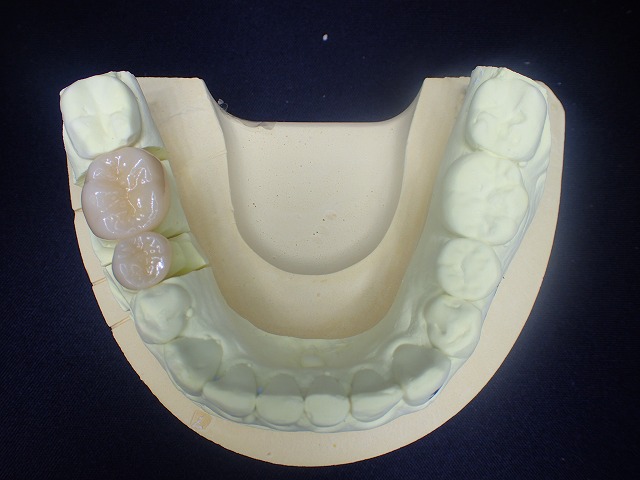

左側のcad/cam冠をジルコニアクラウンに交換

ジルコニアクラウンに交換

左側のCAD/CAM冠を除去してジルコニアを制作

両側の摩耗したCAD/CAM冠を

ジルコニアクラウンに交換できました。